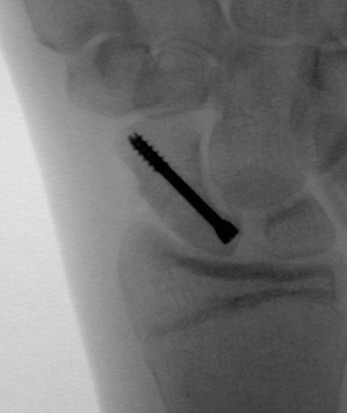

Type A: Stable acute fractures

Type B: Unstable fractures

- B2: complete waist

| B1: Distal oblique | B2: Complete waist | B3: Proximal pole | B5: Comminuted |